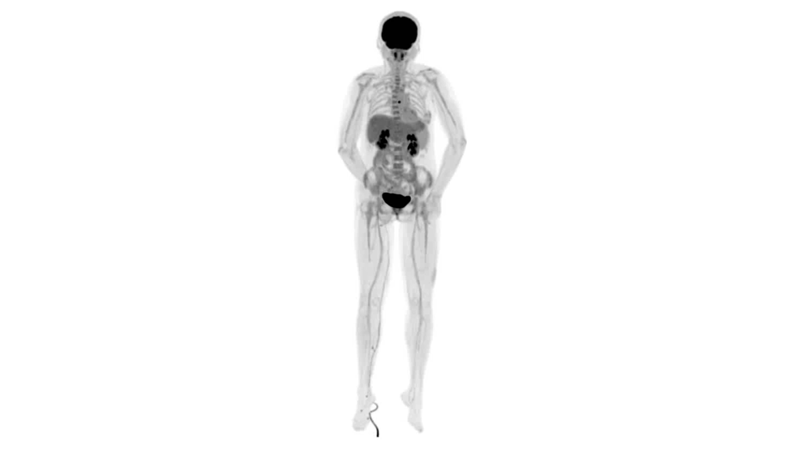

男,45歲,直腸癌術(shù)后9個月,發(fā)現(xiàn)肺占位

臨床診斷:直腸區(qū)術(shù)后改變,復發(fā)伴骶骨受累,雙肺多發(fā)轉(zhuǎn)移